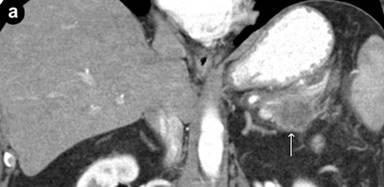

On follow-up in May 2012, the patient reported feeling generally well, except for a new onset of abdominal discomfort, occurring 30 minutes after eating, lasting for 30-60 minutes and associated with diarrhea. He did not complain of other new symptoms. A PET/CT after eight cycles of chemotherapy indicated a near-complete disappearance of the disease at the level of spleen and lymph nodes, but a new mass at the tail of the pancreas measuring 2.0x2.5 cm (Figure 2). Several small (5 mm) hypodense lesions were noted in the liver. These findings were not present on the PET/CT done after the sixth cycle of chemotherapy. To evaluate the focal area of persistent uptake in the pancreatic tail, a CT scan was done in June 2012. It confirmed the mass in the tail of the pancreas, highly suspicious for malignancy (Figure 3). His anemia and thrombocytopenia remained stable. The white blood cell count was within normal range, but showed persistently decreased absolute lymphocyte count. Serum IgG and IgM immunoglobulin levels were decreased to 642 mg/dL (reference range: 782-1,195 mg/dL) and 31 mg/dL (reference range: 53-334 mg/dL), respectively. Serum IgA was normal. CA 19-9 level was elevated at of 1,177 U/mL (reference range: 0-30 U/mL). Biopsy of the pancreatic mass revealed poorly differentiated adenocarcinoma (Figure 4). Immunohistochemical stains of the biopsy specimen revealed positive pankeratin, CK7, CA 19-9, BerEP4, CEA and p63 markers, suggesting primary adenocarcinoma of the pancreas. The patient was considered for possible distal pancreatectomy. However, a preoperative laparoscopic exam showed multiple liver and peritoneal tumor implants, with a biopsy showing pancreatic adenocarcinoma (Figure 4). In addition, the liver biopsy revealed an adjacent atypical lymphoid infiltrate consistent with the patient’s previous mantle cell lymphoma, staining positive for CD20, CD5, BCL-2 and cyclin D1 (Figure 4). The close proximity of the metastatic pancreatic cancer lesions and the mantle cell lymphoma infiltrate was consistent with collision tumors in the hepatic parenchyma (Figure 4).

Figure 3. The coronal (a.) and axial (b.) CT scan views demonstrating a mass in the tail of the pancreas (arrow) characteristic of a pancreatic adenocarcinoma. |